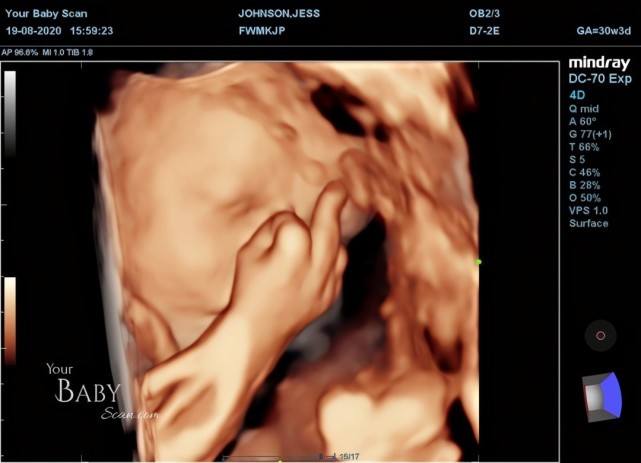

【胎兒動作】英孕婦做超聲波產檢驚見寶寶「舉中指」 媽媽:等他出生我一定提起這件事取笑他!

在產檢的過程中,23歲未婚夫大衛(David Lewis)和杰絲一起細心觀察寶寶動態,並形容兒子開頭有些害羞地把臉遮起來,有時還做出類似「打喊露」的動作,在結束產檢5分鐘前,他們發現兒子做出不雅的手勢:「他對我們舉中指,就好像在說『看夠照片了,別打擾我』。」杰絲表示,舉中指動作沒有維持太久,但認為BB十分搞怪。「等到他出生,我一定會提起這件事取笑他。」